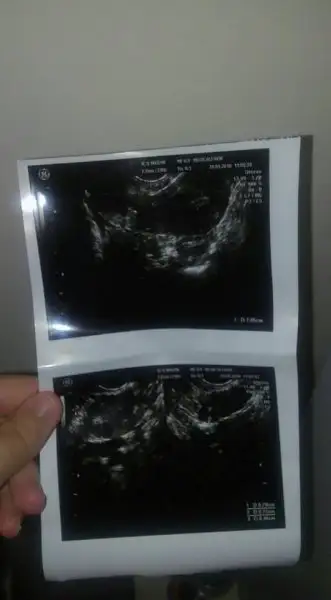

Canim ultrason goruntusunden anliyormusun birsey gostersem

Goster canim ama inan takinti yapiyorsun.cok kurcalama olan sagligini da bozacaksin.bende de akinti ve yanma problemi var gecmiyor.bu arada ben cokmsukur cok kolay hamile kaldim hatta egrafomdakiler bile sasirdi evlenir evlenmez oyoe diyim.merak etme sende de bisey yok.

Eklentiler

• 43291010_699595680416284_3719394966271688704_n.webp

43291010_699595680416284_3719394966271688704_n.webp

6,8 KB · Görüntüleme: 37

Cnm bazı yumurtalıklarda pko gorunumu olabılırmıs ama onemlı olan belırtısıymıs eger adet olamama tuylenme kılo artısı kısırlık problemi varsa onemlıymıs aynısı bendede oldu usg doktoru pko dedi ve yumurtalıgın sişmiş dedi hemen jınekologa gıttım onemlı olan belırtı bısey yok dedi ayrıca pko doğuştan oluyo dıye bılıyorum

Adet oluyorum 29 gunde ve saati saatine killanmam sivilcem yok öyle sadece sonrada kanamam azaldi kafama takildi